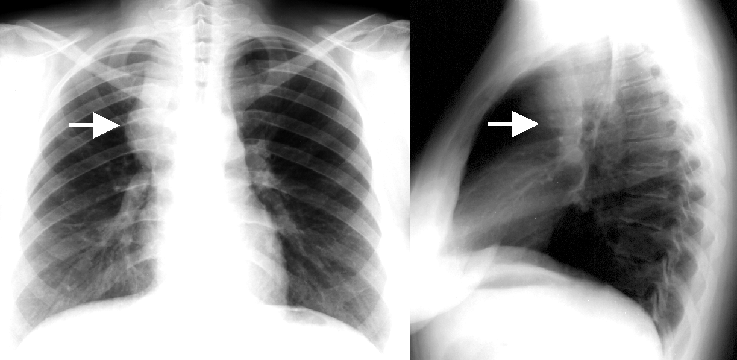

16. Right lobar pneumonia. a.) PA b.) lateral radiograph.

15. Atypical interstitial lobar pneumonia a.) CT b.) radiograph

45 year old man. He had a chill, serious cough, yellow-green tracheal excretion.

Left-sided lymphadenopathy next to the aortic arch on the left. Irregular infiltrations (opacities) in the lung parenchyma in subpleural and LUL dominance. (by the contribution of Zsuzsanna Monostori, MD, PhD)